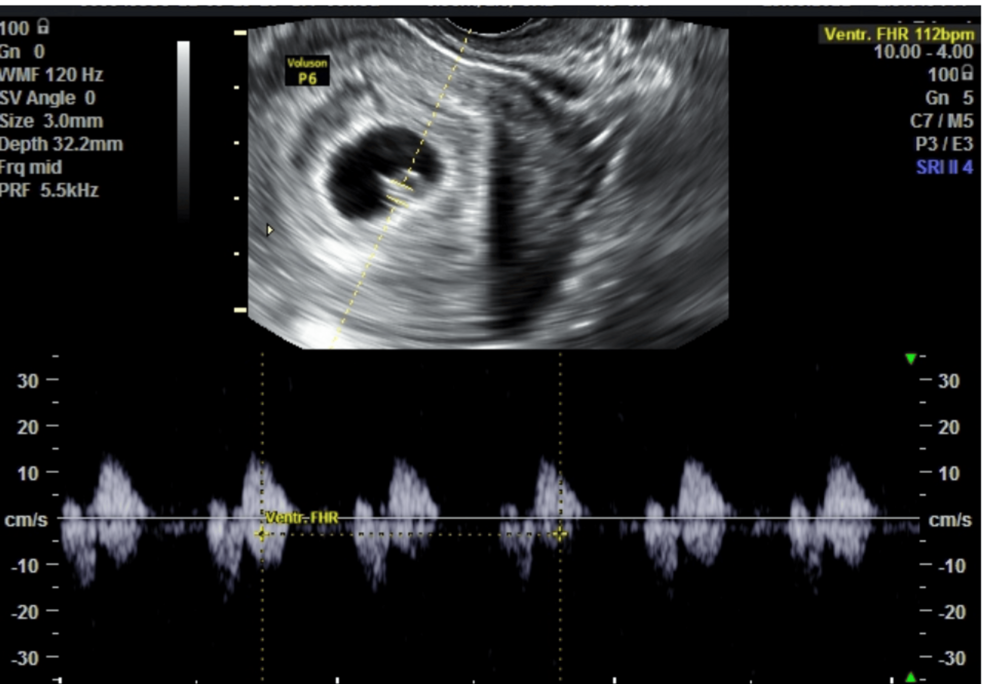

Los hematomas subcoriónicos son acumulaciones de sangre entre el saco gestacional y el revestimiento del útero, y pueden aumentar el riesgo de complicaciones en el embarazo. La investigación se centró en evaluar si la suplementación con ALA y leucina, además del tratamiento estándar con progesterona vaginal, podría mejorar la evolución de estos hematomas.